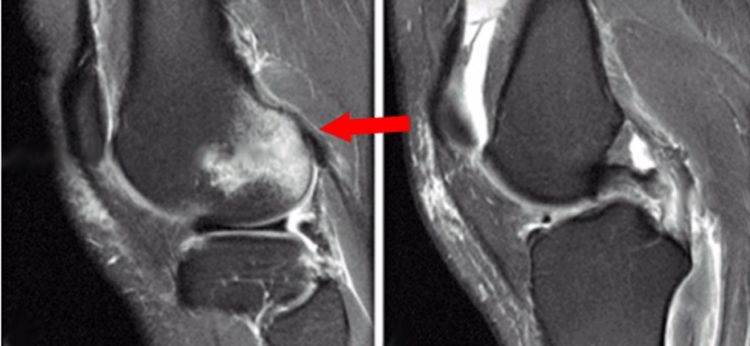

3.后抽屉征:因胫骨后沉引起,除非膝关节脱位,否则后移程度不重。

4.内侧胫骨平台撕脱骨折:胫骨平台前外侧撕脱骨折(Segond骨折)常常合并ACL损伤。而内侧胫骨平台骨折撕脱骨折则常常合并PCL损伤。

5.内后侧胫骨平台的撕脱骨折:国外也进行了相关的研究,主要是半膜肌的牵挂或股骨后髁与胫骨平台内侧缘撞击引起。

国外研究认为膝关节屈曲90°轴向载荷是导致胫骨平台后内侧骨折的一种创伤机制,因暴力的不同,既可合并PCL损伤,也可合并ACL损伤。